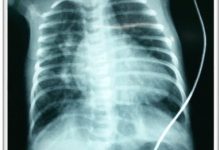

KID’S Heart Foundation is a charitable organization that works for children suffering from congenital heart diseases. When these children grow up to adulthood, they enter into another entity called adult congenital heart disease. KID’S Heart Foundation also continues to work with people suffering from adult congenital heart diseases. The activities include treatment support, rehabilitation, awareness creation, knowledge-based discussion, arrangement of charitable treatment programs from international charities, creation of job opportunities, academic activities for the students, training of students and doctors, etc.